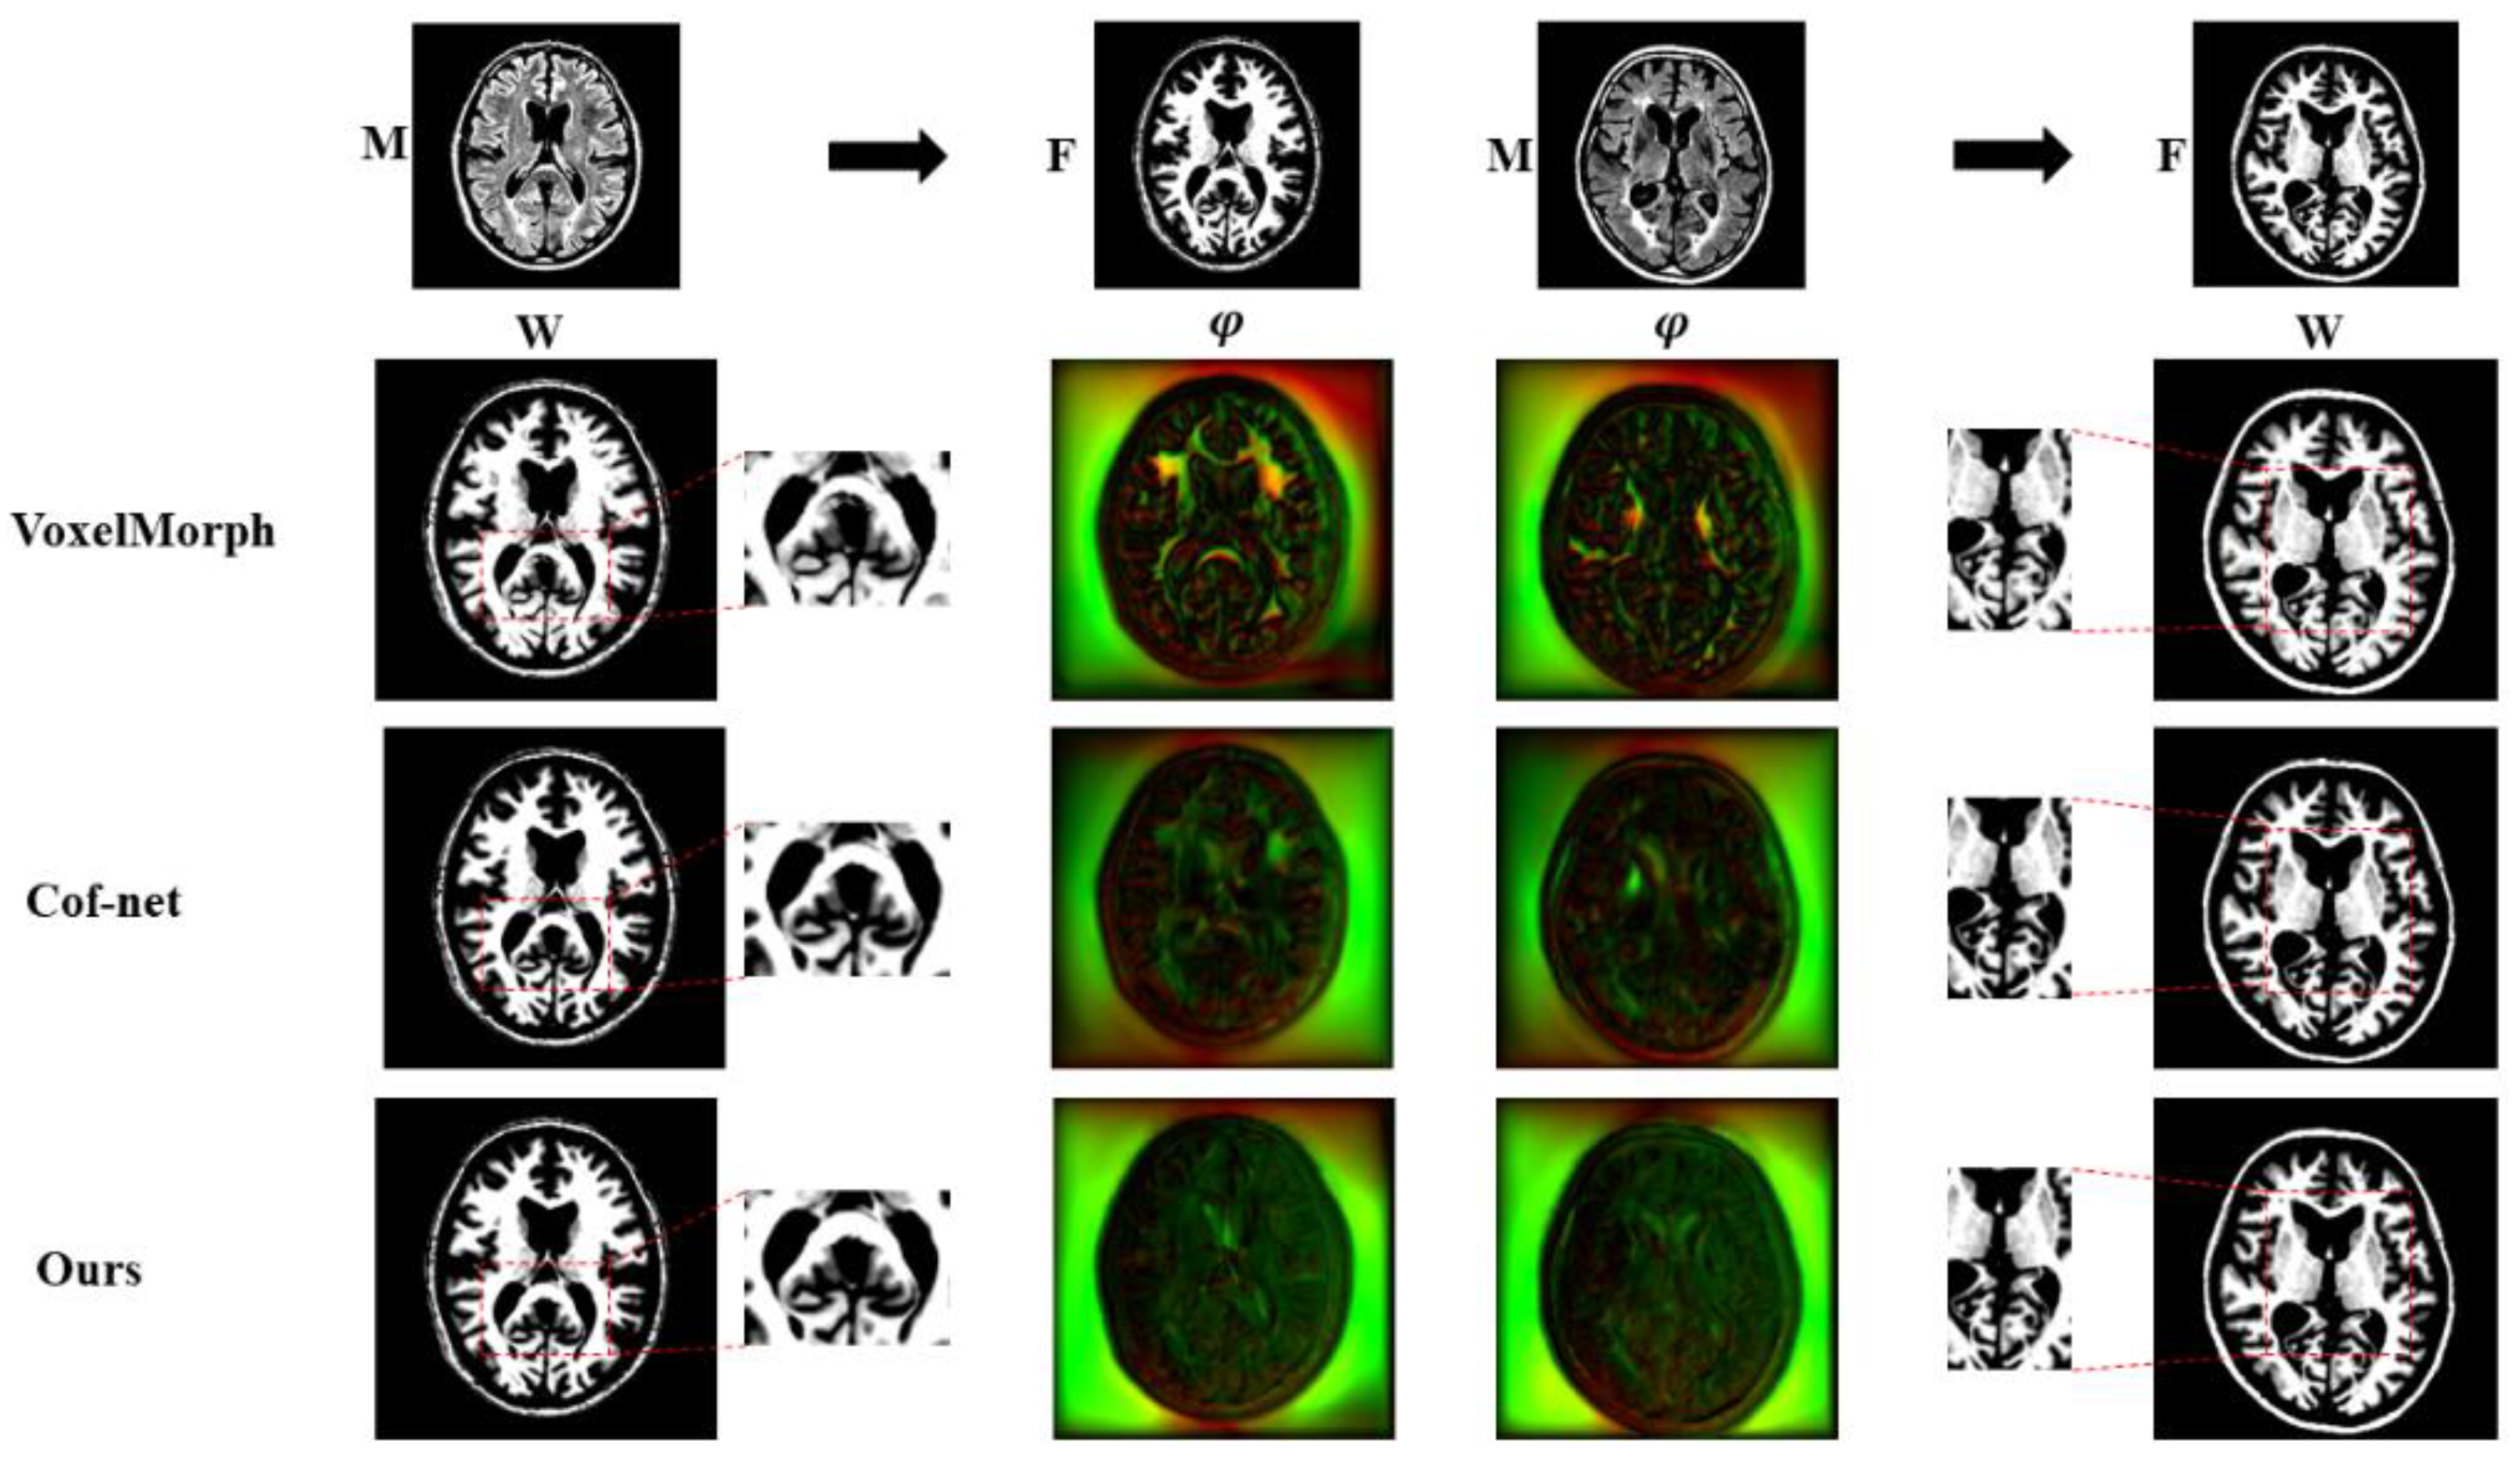

5.3. Comparative Experiments

| Method | DSC (%) | Precision (%) | Runtime (s)/Slice | Det.Jac (%) |

|---|---|---|---|---|

| SyN [1] | 79.48 ± 0.78 | 84.07 ± 0.86 | 2.034 | 0.071 ± 0.007 |

| Voxelmorph [22] | 80.84 ± 0.78 | 91.10 ± 1.18 | 0.558 ± 0.017 | 0.006 ± 0.002 |

| VM-diff [45] | 79.59 ± 2.31 | 86.68 ± 2.52 | 0.423 ± 0.011 | 0.013 ± 0.005 |

| Cof-net [46] | 81.70 ± 3.71 | 90.59 ± 3.05 | 0.367 ± 0.013 | 0.006 ± 0.002 |

| Reverse-net | 85.20 ± 1.18 | 94.41 ± 0.89 | 0.359 ± 0.011 | 0.004 ± 0.001 |